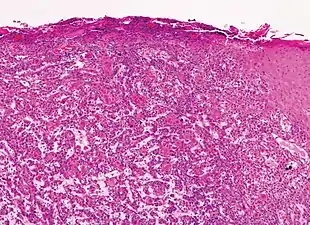

Cutaneous squamous-cell carcinoma tends to arise from actinic keratoses (premalignant lesions); surface is usually scaly and often ulcerates (as shown here). | |

In invasive cSCC, tumor cells infiltrate through the basement membrane. The infiltrate can be somewhat difficult to detect in the early stages of invasion: however, additional indicators such as full thickness epidermal atypia and the involvement of hair follicles can be used to facilitate the diagnosis. Later stages of invasion are characterized by the formation of nests of atypical tumor cells in the dermis, often with a corresponding inflammatory infiltrate.[12]

- Superficially invasive cutaneous squamous-cell carcinoma. These lesions often do not show the marked pleomorphism and atypical nuclei of cSCC in situ, but manifest early keratinocyte invasion of the dermis.[12]

- Invasive nests with characteristic large celled centers. Ulceration (at left) is common in invasive cSCC.